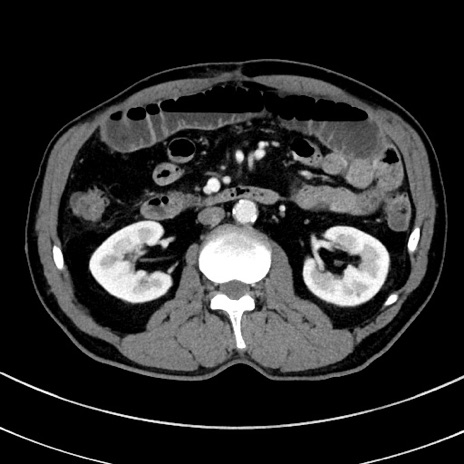

症例8(横断像)

【症例】 60歳代男性

【主訴】 黒色吐物

【現病歴】 4日前から嘔気自覚、2日前の朝食後にも嘔気あり、自分で手で嘔吐反射起こし嘔吐したところ血が混ざっていたため受診。

【既往歴】 5年前汎発性腹膜炎を伴う急性虫垂炎で手術、高血圧、前立腺肥大症、高脂血症

【身体所見】 腹部正中に手術癩痕あり 腹部平坦・軟圧痛なし膨満感あり

【データ】WBC 8400、CRP 4.54